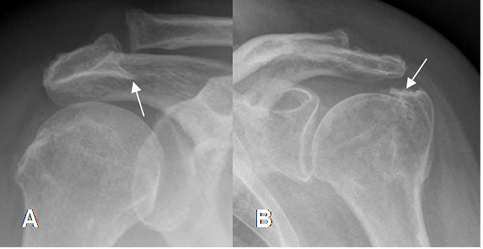

Fig 81. Pinzamiento externo.

A: Rx AP. Formación de osteofito en la parte inferior del acromión.

B: Rx AP. Presencia de osteofitos, sobre la topografía de las tuberosidades.